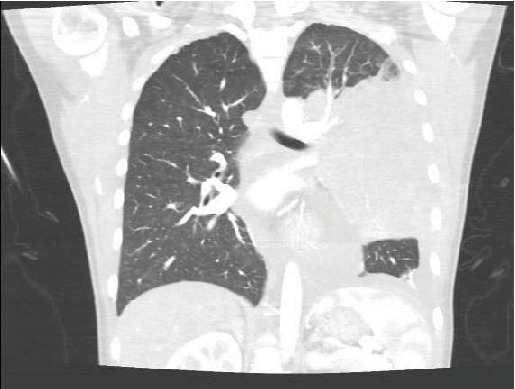

原发性纵隔大b细胞淋巴瘤(PMBCL)是一种高度侵袭性的恶性肿瘤,主要见于30岁左右的女性患者。这种罕见疾病的发病率为百万分之0.4,传统上表现为B型症状或压迫性后遗症,如SVC综合征或呼吸窘迫。在本报告中,我们报告了一位年轻女性的病例,她表现为心悸和心动过速,没有心肺按压症状,诊断为位于左心室的16厘米浸润性PMBCL。

Primary mediastinal large B-cell lymphoma (PMBCL) is a highly aggressive malignancy primarily observed in female patients during their third decade of life. This rare condition, with an incidence of 0.4 per million, traditionally presents with B symptoms or compressive-based sequela such as SVC syndrome or respiratory distress. In this report, we present the case of a young female who presented for palpitations and tachycardia without cardiopulmonary compressive-based symptoms diagnosed with a large 16-cm infiltrative PMBCL localized in the left ventricle.